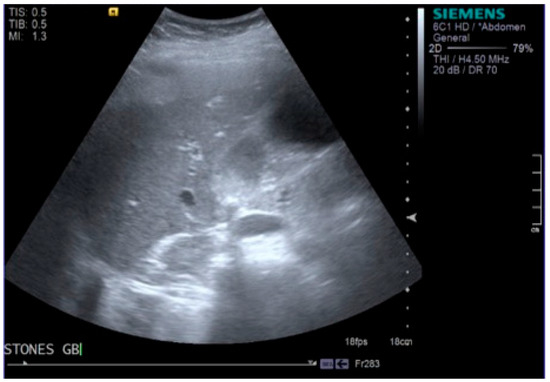

2. Case Report